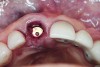

The master cast and abutment were returned to the laboratory for fabrication of the restoration (Figure 15). An all-ceramic crown (e.max®, Ivoclar Vivadent) was fabricated on the custom abutment; it matched the contours of the adjacent central incisor. After completion of custom shading, the definitive abutment and crown were returned to the restorative dentist. The abutment was tried in (Figure 16), and a radiograph was taken to confirm complete seating between the abutment/implant and the crown/abutment. The definitive abutment screw was torqued to 20 Ncm, and the screw-access opening was blocked out with Teflon tape.

The crown was inserted and secured with a luting composite (Multilink® Automix, Ivoclar Vivadent) (Figure 17); a radiograph confirmed complete removal of excess cement (Figure 18). At the 4-month follow-up appointment, the soft tissues were healed within normal limits, and the patient was pleased with the esthetic outcome of the definitive restoration (Figure 19 and Figure 20).

Fig 16. Try-in of the definitive titanium-nitride–coated abutment.

Figure 16

Fig 19 and Fig 20. Four-month follow-up appointment. The soft tissues had healed within normal limits (Fig 19), and the patient was pleased with the esthetic outcome of the definitive restoration (Fig 20).